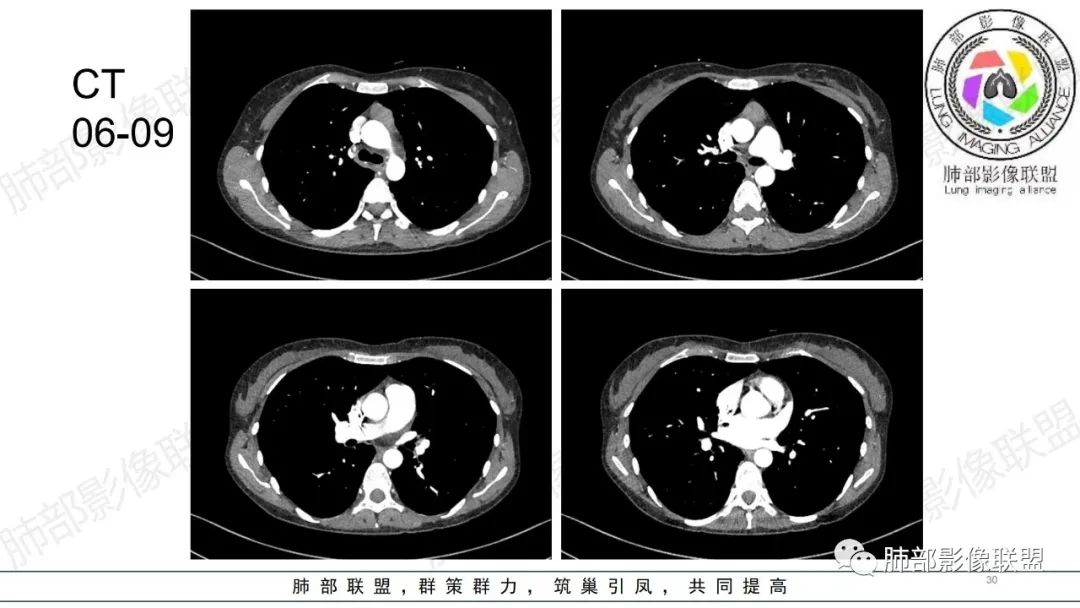

34岁女性患者,“哮喘”病史30年,近期有可疑刺激性气体吸入史;因乏力半年,咳嗽、憋气、发热4天就诊;6.1CT提示双肺广泛毛玻璃影及粟粒样结节,胸膜下闲置及血管周闲置,可见树丫征,部分小叶间隔增厚。考虑:1.过敏性肺泡炎,有可疑刺激气体接触史,胸膜下闲置,广泛毛玻璃影,地图样分布,粟粒结节边界模糊,支持过敏性肺泡炎,但糖皮激素治疗效果不佳,且动态复查血常规血红蛋白进行性降低,过敏性肺泡炎 不符合;2.肺含铁血黄素沉积症:患者30“哮喘”病史,可能为肺含铁症状,肺部CT提示双肺弥漫毛玻璃影及粟粒结节影,中下肺明显,肺底部分小叶间隔增厚,近期咳嗽、憋气、发热,血常规血红蛋白进行性下降,考虑肺含铁急性期症状,但临床无咯血症状,肺含铁不典型。综合考虑:肺含铁血黄素沉积症>过敏性肺泡炎。

年轻女性 ,急性喘息发热,肺部影像弥漫磨玻璃密度,部分细小腺泡结节,胸膜下黑线显示,短期复查,病变密度增高,下肺明显,血管周围肺组织累及较少、且逐渐成小叶间隔分布。考虑弥漫肺泡内病变,并经淋巴道转移,下肺比上肺明显,多为免疫细胞功能下肺较强。1.过敏性肺泡炎,有相关病史,三层密度特点、头尾测分布,符合。2 肺泡微石症,多有钙化,且缓慢起病,病程不太符合,放待排。3 吸入相关肺损伤,有病史,疾病演变过程也符合渗出-肉芽肿改变,建议详细询问病史。4 感染性病变,结核?病变气道分布为主,如此弥漫且没有树丫不符合。5.巨细胞病毒,可以磨玻璃 结节 改变,没有免疫缺陷病史。最后考虑吸入所致 1过敏性肺泡炎、吸入性肺损伤 鉴别肺泡微石症。

肺内气腔磨玻璃结节,肝脾肿大,治疗后间质改变,弥漫大B可能